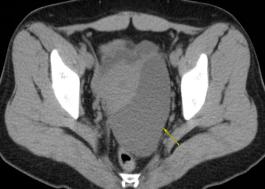

术后组织送病理检查,HE染色和免疫病理提示:考虑多囊性间皮瘤(图3),免疫病理:癌胚抗原M2A(D2-40)(+),抗平滑肌抗体(SMA)(-),血小板内皮细胞粘附分子(CD31)(-),高度糖基化I型跨膜糖蛋白(CD34)(-),Wilm肿瘤1(WT-1)(+),角蛋白(CK)(+),钙结合蛋白(+),细胞增殖相关核抗原(Ki-67)约1%(+)(图4)。

妇科蛋白膜怎么用这种妇科肿瘤无特异性,复发率高,有这些症状的姐妹小心_https://www.jmylbn.com_新闻资讯_第3张图3 肿瘤组织HE染色,放大10倍妇科蛋白膜怎么用这种妇科肿瘤无特异性,复发率高,有这些症状的姐妹小心_https://www.jmylbn.com_新闻资讯_第4张图4 肿瘤组织,免疫组化染色,

放大10倍,CK染色阳性